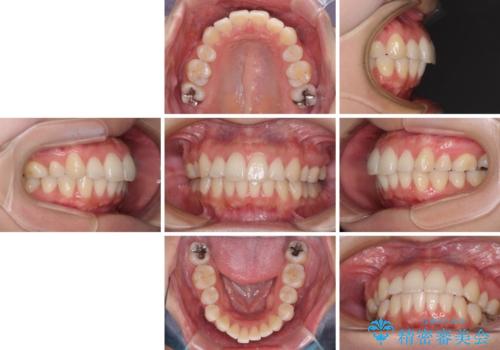

- 抜歯矯正の後戻りで前歯が突出してきていることを気にして来院された患者様です。

口元の突出感を改善するにあたり、抜歯矯正は行うことができないため、奥歯の後方移動とIPR(歯と歯の間を削る)により達成することとしました。

再度後戻りしたときに対応しやすいよう、インビザラインにて矯正治療を行うこととしました。

しっかりと装着時間を守り、ゴムかけにも協力していただいたので、口元を引っ込めることができました。